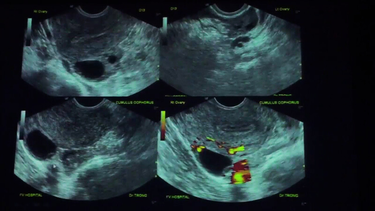

Siêu âm theo dõi nang noãn

Siêu âm là phương pháp giúp quan sát trực tiếp sự phát triển của nang trứng trong buồng trứng. Đây là cách xác định ngày rụng trứng có độ chính xác cao, đặc biệt hữu ích cho những người có chu kỳ kinh nguyệt không đều. Tuy nhiên, phương pháp này cần được thực hiện tại các cơ sở y tế có chuyên môn và thiết bị phù hợp.